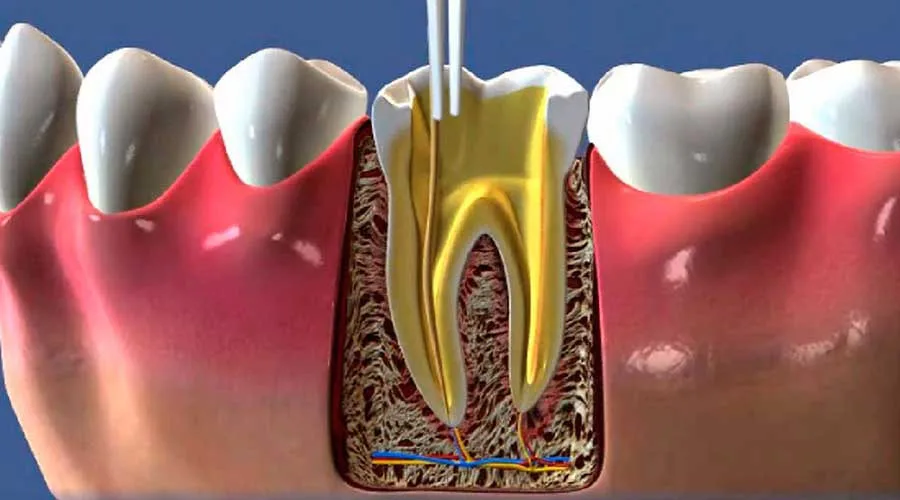

Quando a polpa dentária está inflamada ou infectada, a dor pode ser insuportável.

O tratamento remove a polpa infectada e desinfeta os canais radiculares.

Durante o tratamento, você pode esperar um procedimento tranquilo e seguro.

O dentista irá anestesiar a área afetada para assegurar seu conforto.

Após a limpeza e desinfecção, o dente será obturado para proteção.